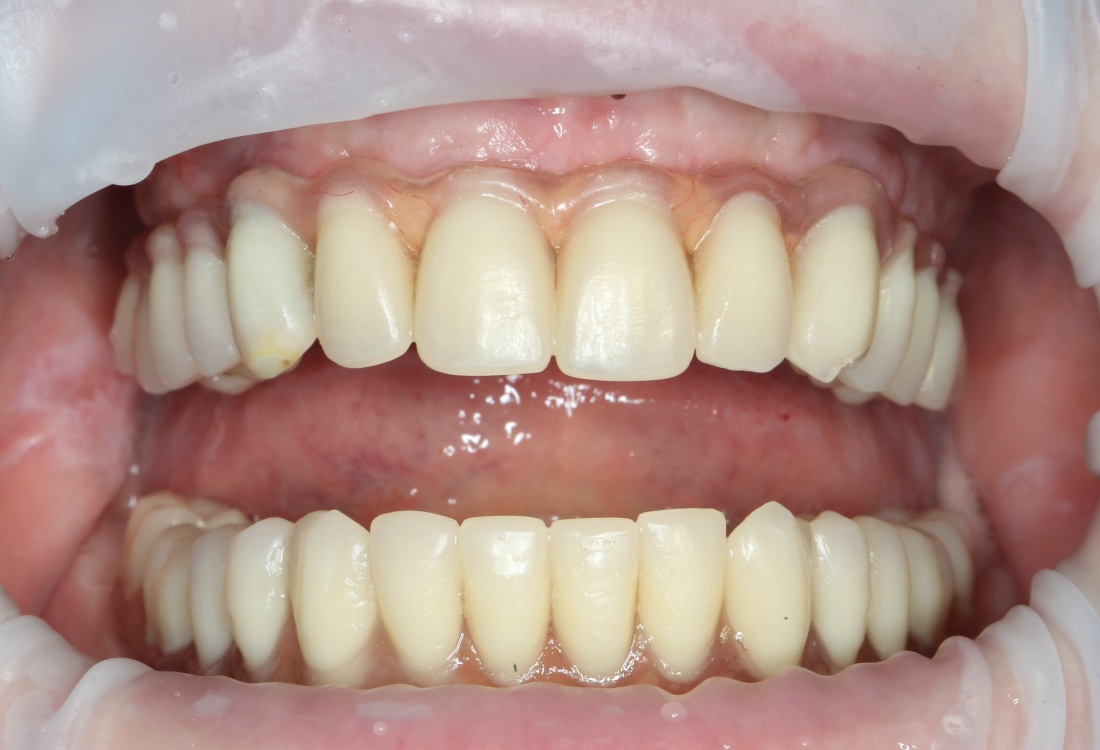

Рекомендации по установке имплантов. Для всех. Часть V.